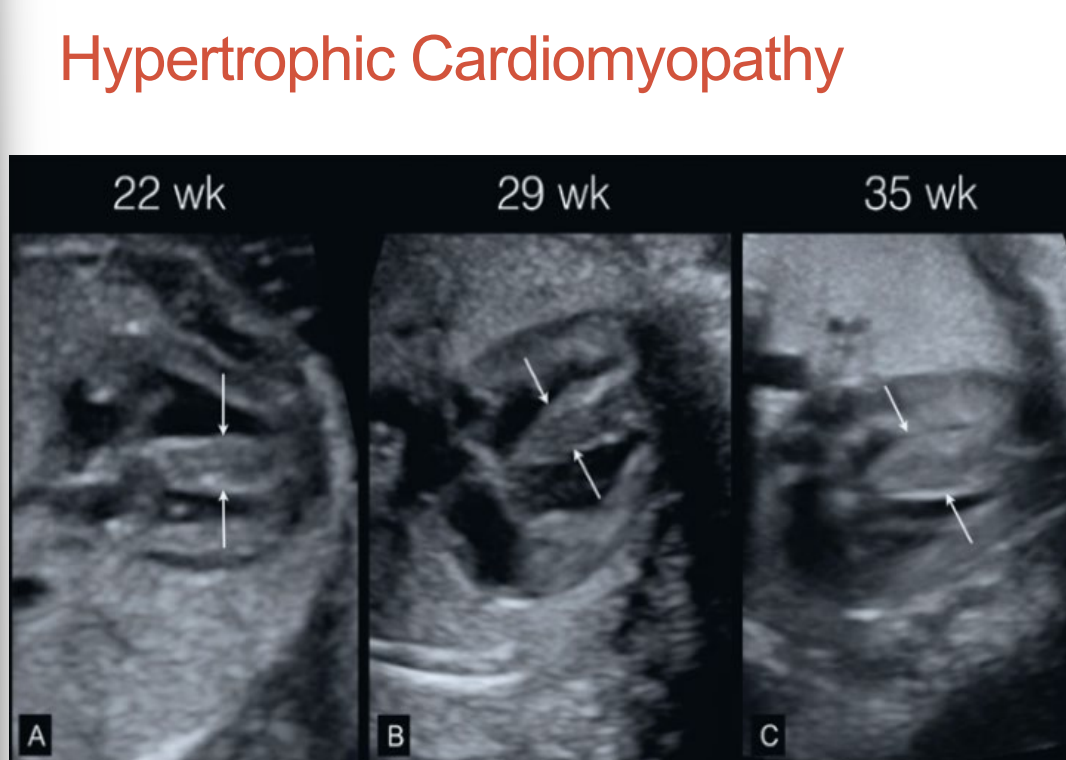

Hypertrophic Cardiomyopathy - what is it?

Concentric hypertrophy of both ventricles •

Small ventricular chamber size with normal function •

Left ventricular outflow track obstruction can occur •

Pericardial effusion is common •

May be caused by diabetes, storage diseases, and Noonan Syndrome •

Can resolve or lead to heart failure, hydrops, and in utero death